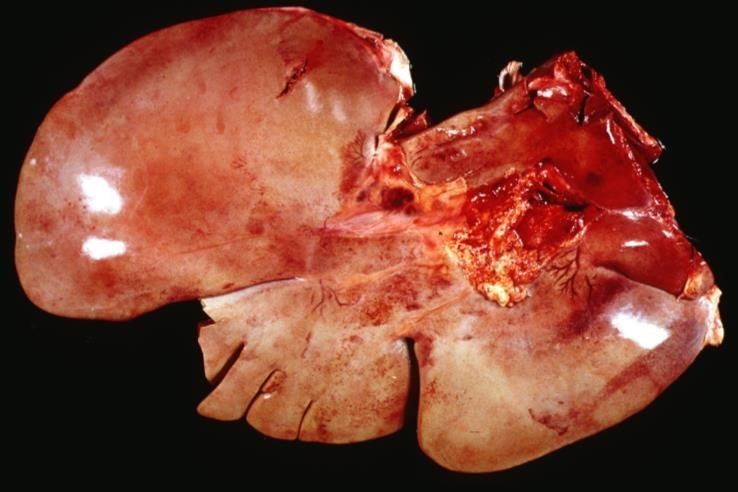

Describe this lesion

The surface and deep tissue is focally extensively pale tan, with about 80% of the hepatic tissue being affected. The tissue itself is extremely friable when touched.

Diffuse moderate subacute hepatic lipidosis